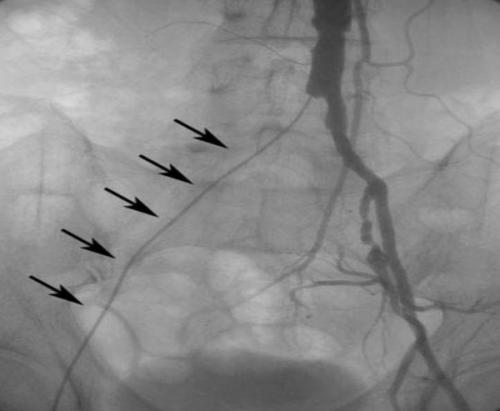

Инструментальная диагностика

Измерение лодыжечно-плечевого индекса — неинвазивный метод обследования артерий конечностей. Его суть заключается в измерении систолического артериального давления на плечевых артериях и артериях стопы после лежания на кушетке в течение 10 минут. Данное исследование достаточно достоверно, поэтому его можно использовать как метод первой линии.

Индекс ≤ 0,9 указывает на заболевания нижних конечностей. Высокие значения говорят о повышенном тонусе артерий, который характерен пациентам с сахарным диабетом и/или хронической болезнью почек. При пограничном значении требуется тест с нагрузкой.